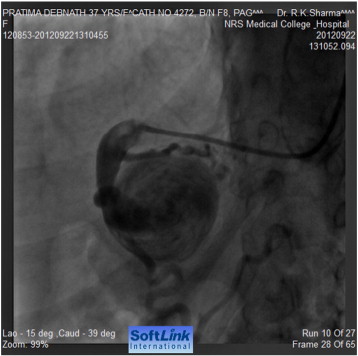

As the patient was having nagging pain at the site of aneurysm, there was a risk of rupture of the aneurysm. As she had a very high surgical risk because of high BP, poor general health and risk of renal compromise; transcatheter closure of aneurysm was planned. An Amplatzer Vascular Plug II was deployed in the distal end of the feeding collateral branch of the gastroduodenal artery through right brachial artery and the aneurysm was successfully closed (Fig. 6 ;  Fig. 7). Since then, the loin pain disappeared and surgical revascularization by aorto-iliac or aorto-femoral bypass grafting is being considered for relief of lower limb ischemic symptoms.

Plug inserted.

Fig. 6.

Successful closure of the feeding vessel.

Fig. 7.